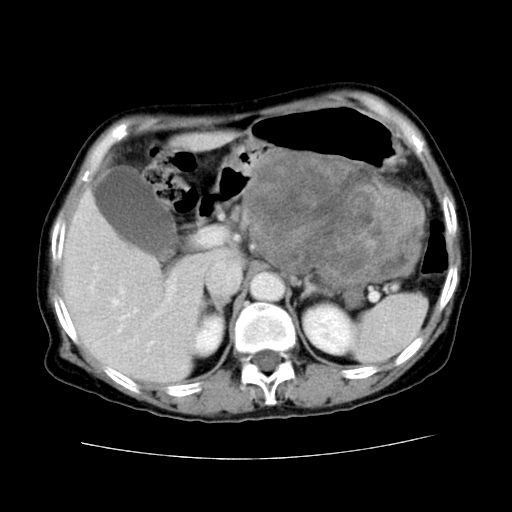

女性,72岁。

主诉中上腹部疼痛不适1年余。

该例有几个特点需注意:

1.肿瘤大而边界清

2.内部有钙化

3.强化时间较长

4.这么大的肿瘤对周围的血管无侵犯

以上几条均与胰腺癌不符

故考虑:胰岛细胞癌

1、这个病例确实有点难。影像主要显示胰腺体尾部占位,我们当初也是诊断胰体尾部囊腺癌可能性大,而且读片会上也很多人这么诊断的。

2、手术所见:打开腹腔发现胃与胰腺体尾部可见肿块,大小约10×8×11cm,质硬,不可推动,周围血供丰富。术中诊断:胃肿瘤侵及胰腺体尾部。

1)、胃小弯侧胃肠间质瘤(考虑恶性),瘤体大小13.5×7×6.5cm,上下切缘阴性。

2)、胃小弯1只、幽门下2只淋巴结慢性炎。免疫组化:cd117(+)、cd34(+)、sma(+)、desmin(-)、s-100(-)、ki-67<10%(+).

4、这个肿瘤太大了,而且密度不均性强化,从这点我们应该不能单纯诊断胰腺癌,而应想到目前流行的胃肠道间质瘤。这个肿瘤主要发生于胃壁浆膜层,所以显示与胃壁关系不是很紧密,故而大多认为是胰腺癌。